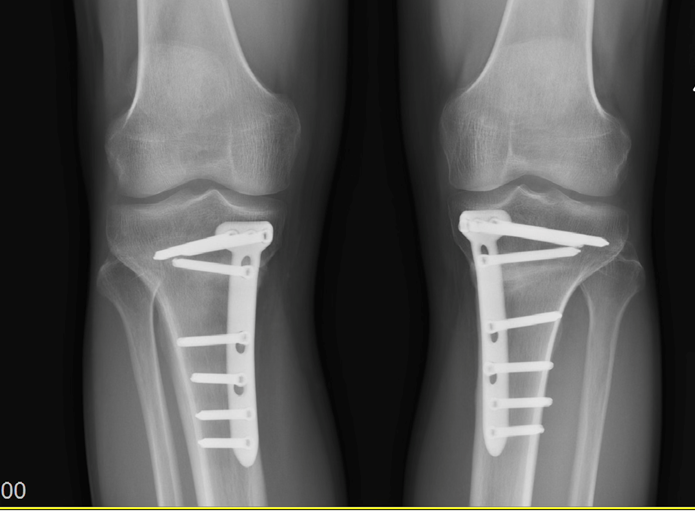

Osteotomia to zabieg chirurgiczny, podczas którego chirurg przecina kość i koryguje jej kształt lub ustawienie, aby wyrównać oś mechaniczną kończyny dolnej. W przypadku kolana najczęściej wykonuje się osteotomię kości piszczelowej (High Tibial Osteotomy – HTO) lub kości udowej (Distal Femoral Osteotomy – DFO)3. Celem zabiegu jest przeniesienie obciążenia ze zużytego, chorego przedziału stawu na przedział zdrowy, co daje szansę na odciążenie uszkodzonej chrząstki i opóźnienie lub całkowite uniknięcie potrzeby wszczepienia sztucznego stawu. W przypadku szpotawości najczęściej wykonuje się osteotomie kości piszczelowej, w przypadku koślawości kolana osteotomie kości udowej. W przypadkach dużej deformacji osi, konieczne bywa wykonanie zabiegu zarówno na kości udowej jak i piszczelowej.

Rozwój technologii znacząco poprawił precyzję i wyniki osteotomii. Współczesne podejście obejmuje:

- Planowanie przedoperacyjne z użyciem zaawansowanych programów komputerowych – pozwala to na precyzyjne określenie wielkości korekcji

- Nawigację komputerową śródoperacyjną – umożliwia rzeczywistą kontrolę korekcji w trakcie zabiegu

- Przygotowanie w oparciu o tomografią komputerową indywidualnego dla pacjenta instrumentarium (ang. patient-specific instrumentation PSI ) – zapewniającego idealną precyzję korekcji i cięcia kości.